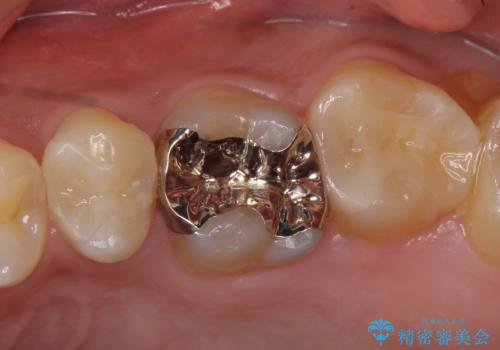

![[嘔吐反射がひどく義歯がつけられない] 臼歯部インプラント補綴 の症例 治療後](https://seimitsushinbi.jp/wp/wp-content/uploads/2020/03/27f48952c3f36e797e751ba818028a44-1-500x350.jpg?v=1585390198)